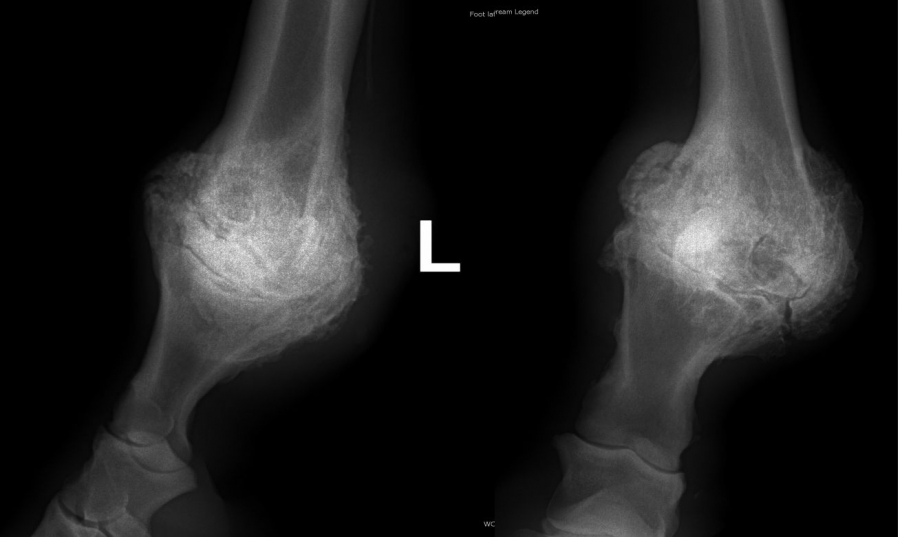

Ankylóza spěnkovýho kloubu